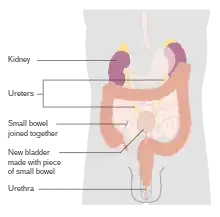

Untreated, non-muscle invasive tumors may gradually begin to infiltrate the muscular wall of the bladder (muscle invasive bladder cancer). Tumors that infiltrate the bladder wall require more radical surgery, where part (partial cystectomy) or all (radical cystectomy) of the bladder is removed (a cystectomy) and the urinary stream is diverted into an isolated bowel loop (called an ileal conduit or urostomy). In some cases, skilled surgeons can create a substitute bladder (a neobladder) from a segment of intestinal tissue, but this largely depends upon a person's preference, age of the person, renal function, and the site of the disease.